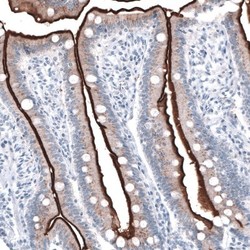

- Immunohistochemistry-Paraffin: ACE-2 Antibody (CL4035) [NBP2-59037] - Staining of human duodenum shows strong immunoreactivity in apical membranes of glandular cells.

- Immunohistochemistry-Paraffin: ACE-2 Antibody (CL4035) [NBP2-59037] - Staining of human duodenum shows strong positivity in apical membrane of glandular cells.